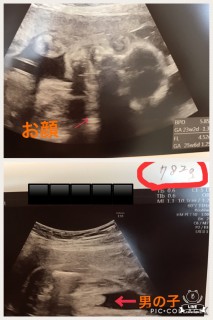

今日、性別が分かりました!男の子でした。大きさは782グラム。胎動も激しいです!今日は炭酸飲んで血液検査?でした。次からは2週間ごとの検診です。